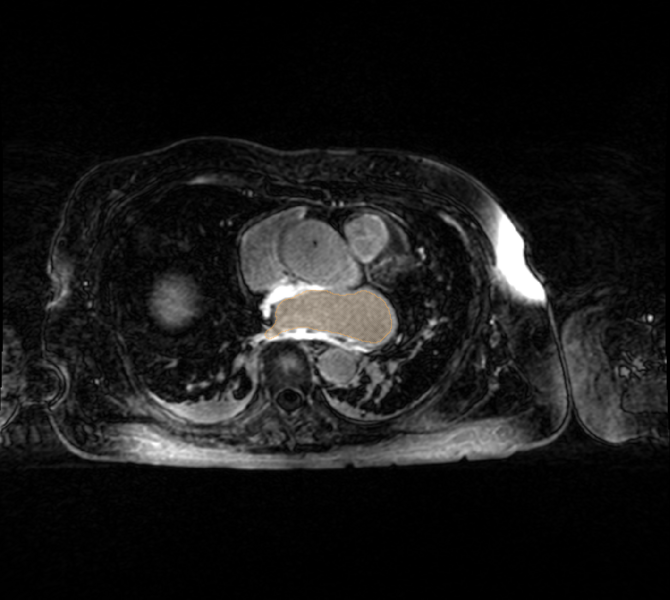

LGE-MRI scans acquired immediately post-ablation pose extra challenges for registration; often times, edema and other acute physiological changes effect the washout kinetics of the contrast agent and the morphology of the LA. Here the MR contrast agent has not entered into some regions of the LA wall - "no-reflow" non-enhancing regions.